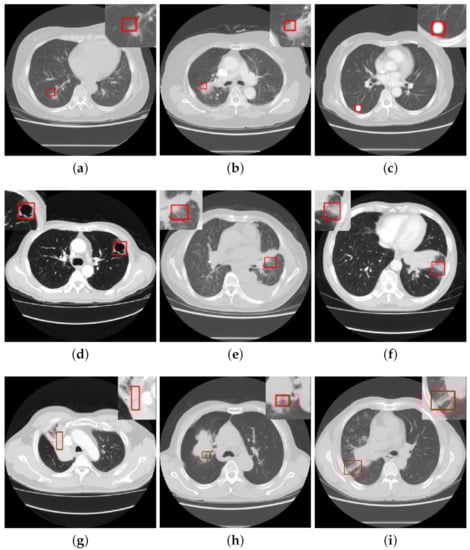

2.3. The Overview Framework for Detection of CISs

- CISs detection. While having achieved great progress, most of the present approaches largely focus on CISs classification tasks. There is a lack of research focusing on object detection of CISs. However, people are more interested in lesion detection tasks in medical imaging as opposed to classification tasks, which may be for the following reasons: objection detection networks are much more complex than classification networks and require higher quantity and quality of data. However, there is a wide variety of signs of lung lesions, and as the differences between signs are small, it is very difficult to accurately detect and quantify them.